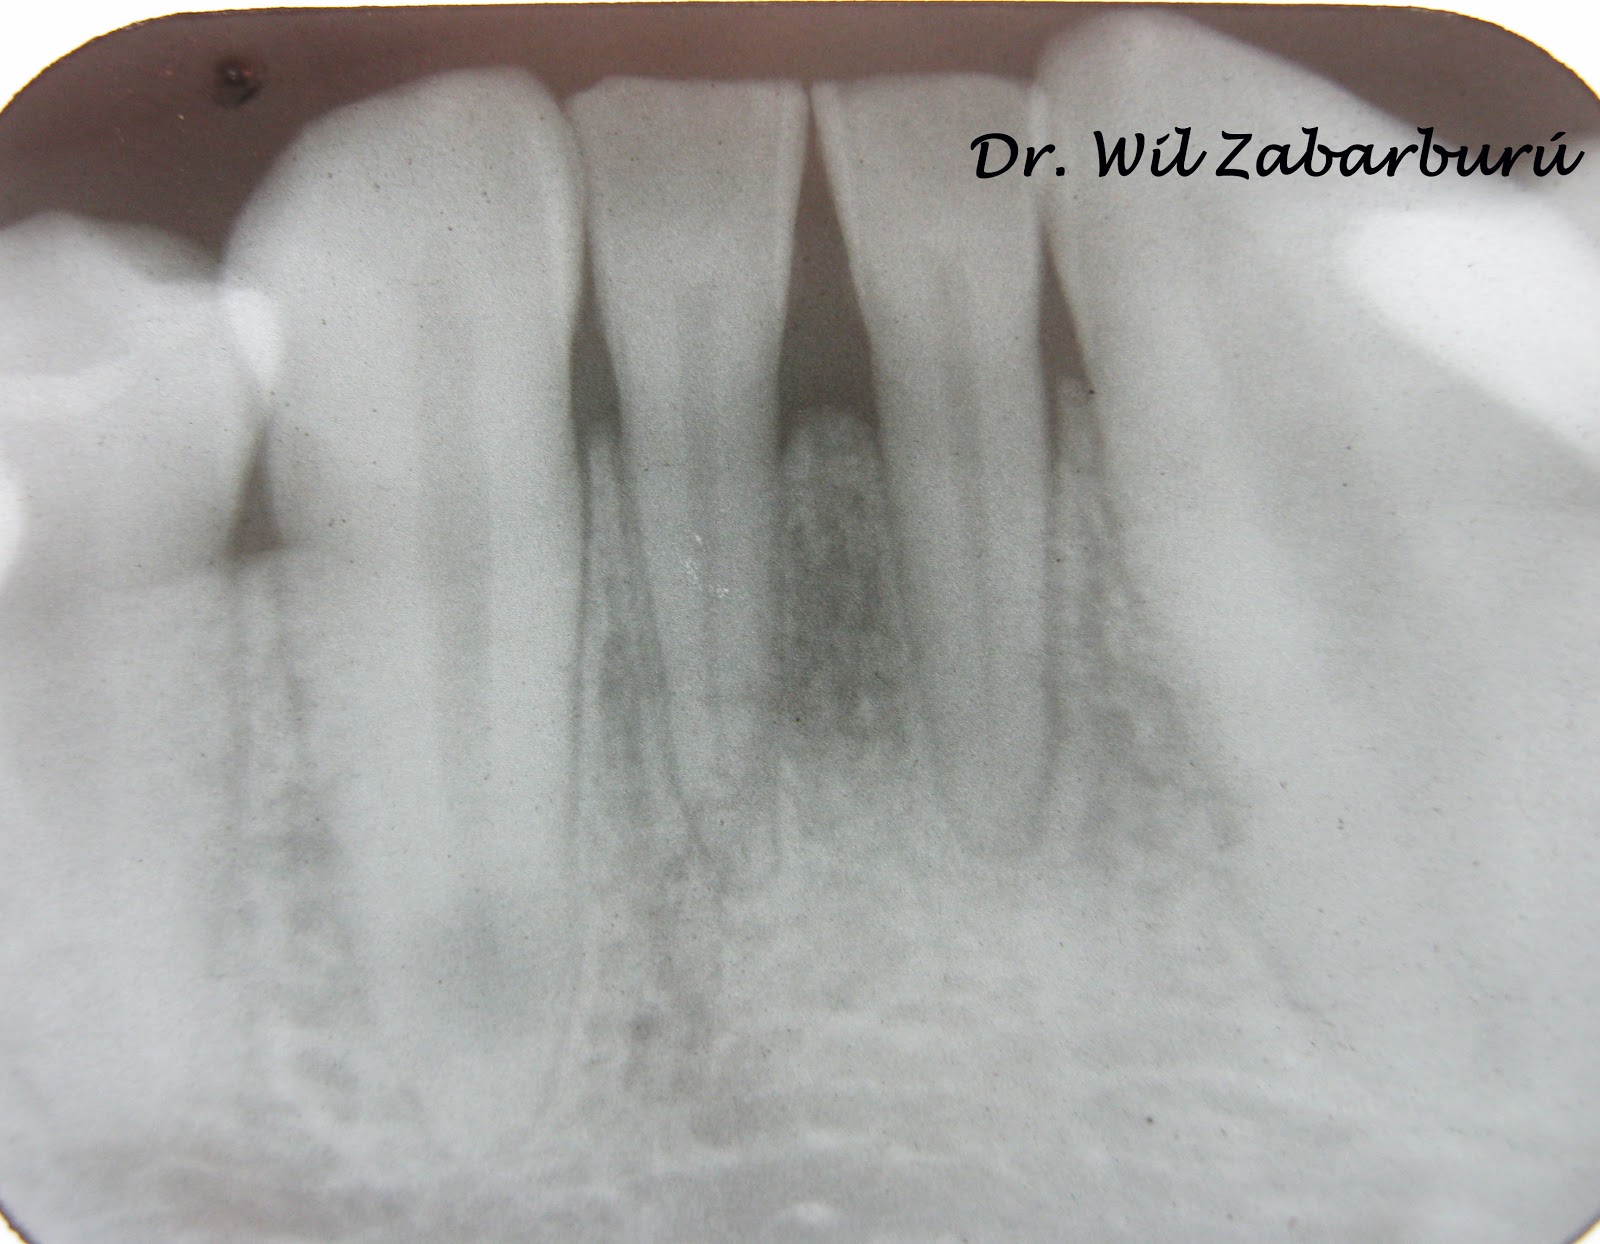

Se nota la presencia de una leve tumoración y color oscuro más intenso en la mucosa de la zona correspondiente a la pieza dentaria 1.1.Se le realiza una radiografía oclusal de la arcada superior y efectivamente se ve la corona de la piza 1.1 retenida por tejido blando.